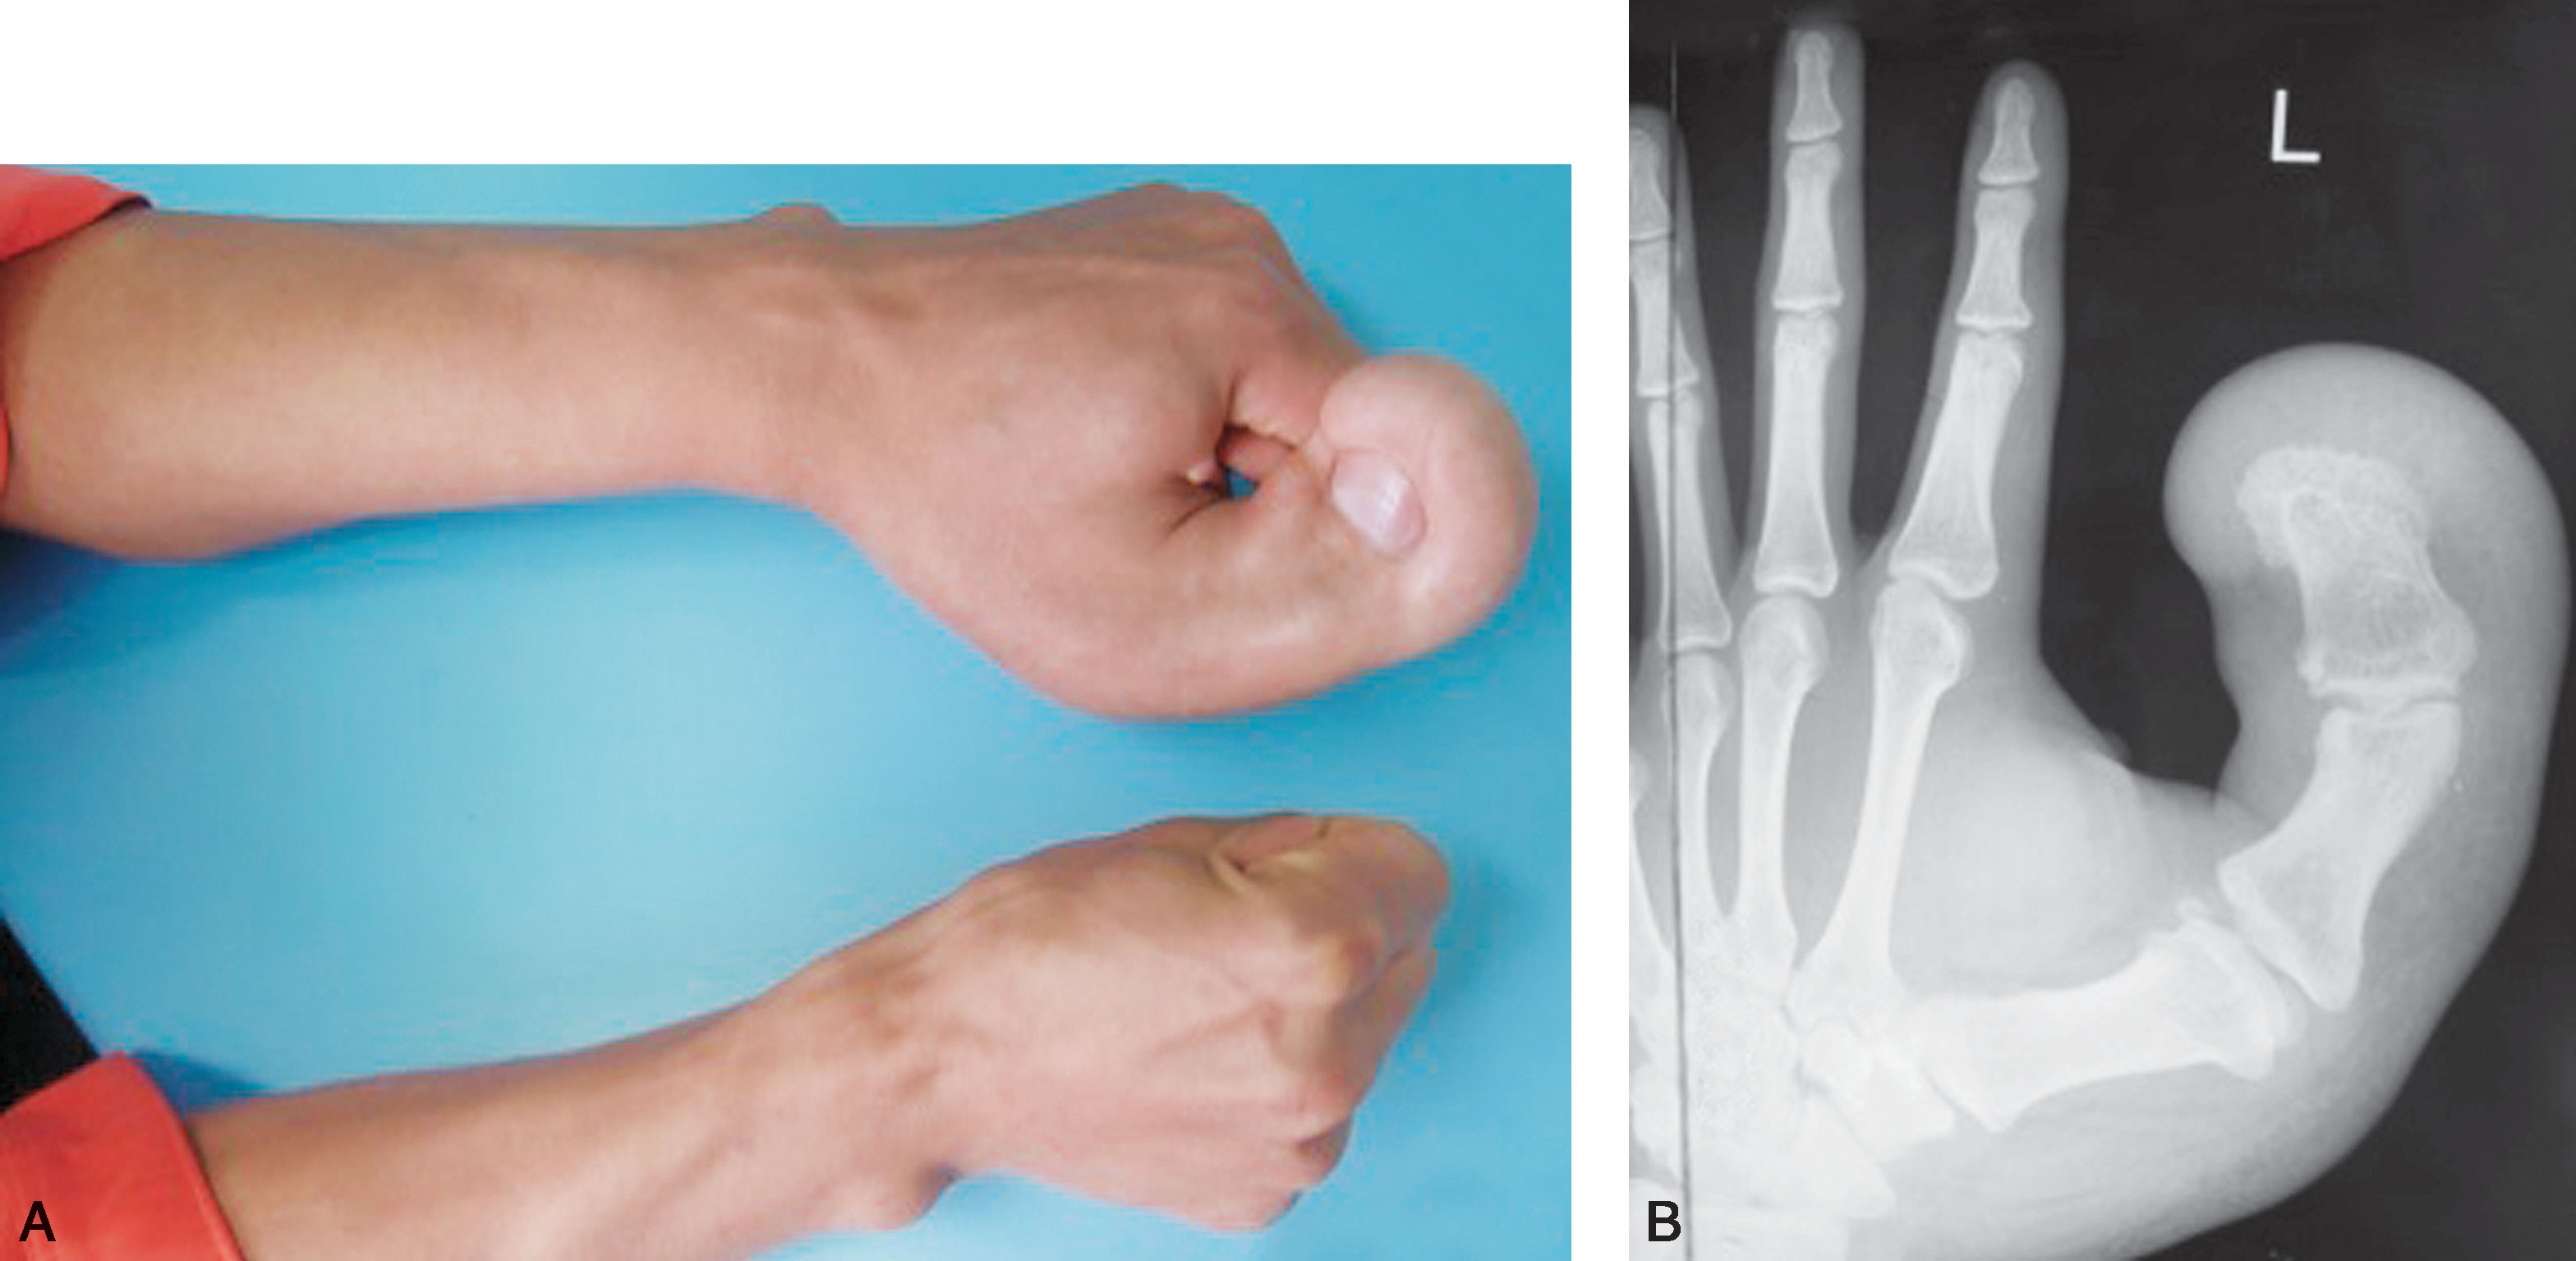

3.巨指(图1-2-42、图1-2-43)。

图1-2-42 原发性巨指症病例

A.左拇指原发性巨指症;B.X 线片显示拇指骨关节肥大,软组织阴影广泛

图1-2-43 继发性巨指症病例

A.左中、环、小指继发性巨指症(骨软骨瘤病),波及手掌;B.X 线片显示右手多发骨软骨瘤